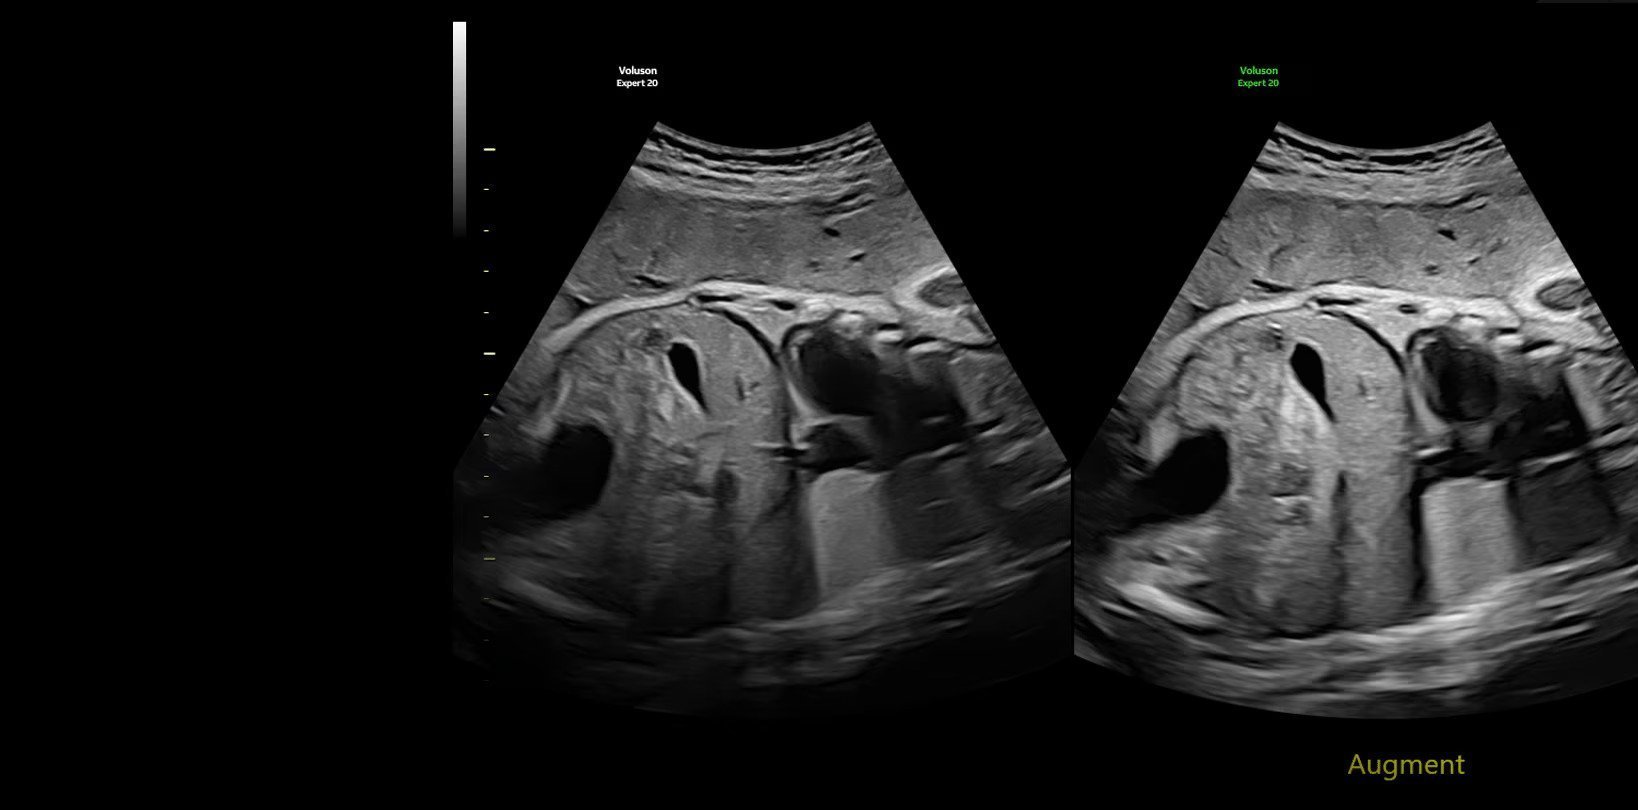

Voluson Expert 22 построен на совершенно новой высококачественной платформе Lyric Architecture, которая использует формирование луча на основе графики. Voluson Expert 22 создан для визуализации, которая сочетает в себе исключительное качество изображения, превосходные технологии объемного ультразвука и возможности искусственного интеллекта.

- Генерирует новые уровни проникновения, разрешения и частоты кадров для легкого выявления тонкой анатомии в 2D/3D/4D

- Обеспечивает однородность всего изображения с повышенным пространственным и контрастным разрешением

- SonoAVC — Sono Automated Volume Count — программа для автоматического расчета размеров и объема анэхогенных образований/структур в режиме объемной реконструкции. Включает программу для расчета фолликулов и программу для расчета других анэхогенных структур для механических и электронных объемных датчиков